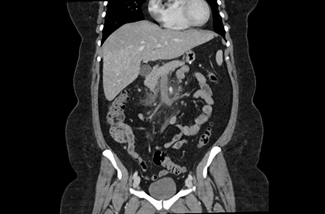

The initial physical examination showed a patient in discomfort but with normal vital signs. The abdominal palpation revealed epigastric tenderness without guarding or without other signs suggestive of acute abdomen. Surgical sites appeared to be well-healed, clean, and dry with no evidence of drainage or dehiscence. The laboratory analyses showed elevated inflammatory parameters (13,500 leukocytes and a C-reactive protein level of 123,20 mg/dL) and normal levels of amylase and lipase. A contrast-enhanced abdominopelvic computed tomography (CT) scan (Figures 1, 2, and 3) showed a dilatation in the mesenteric vessels, particularly the superior mesenteric vein, which had a luminal filling defect near its confluence with the splenic vein. The CT scan also revealed thickening of the adjacent adipose tissue, albeit without signs of intestinal ischemia. The patient was admitted to ward and started on LMWH 100 mg every 12 hours along with reinforced IV hydration. After three days in the hospital, she was discharge home asymptomatic. Anticoagulation therapy was continued with LMWH for one month before transitioning to a non-vitamin K antagonist oral anticoagulant (NOAC), specifically Apixaban 5 mg every 12 hours, and the use of estrogen for birth control was discontinued. At the three-month follow-up, the patient had lost 20 kg and was scheduled to repeat the CT scan and to discontinue anticoagulation therapy approximately six months after the thrombotic event.

The most common presentation of PMVT is nonspecific, often characterized by a diffuse abdominal pain, accompanied by nausea, vomiting, and changes in bowel habits.12 Enhanced abdominal CT with intravenous contrast, is the gold standard method for diagnosing PMVT, boasting a high sensitivity of 90%. (10) In the CT scan, we can identify the affected vascular territory and determine if there is intestinal compromise. The presence of free fluid, pneumoperitoneum, or indirect signs of intestinal ischemia (non-enhancing or hypo-enhancing bowel wall after contrast injection, pneumatosis intestinalis, portomesenteric venous gas and alteration in wall thickness) are warning signs that should prompt urgent surgery.13